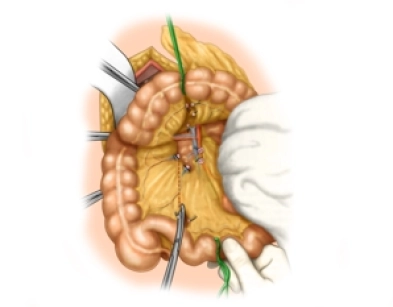

Resektion eines infrarenalen Bauchaortenaneurysmas und Rohrprothesen-Interposition